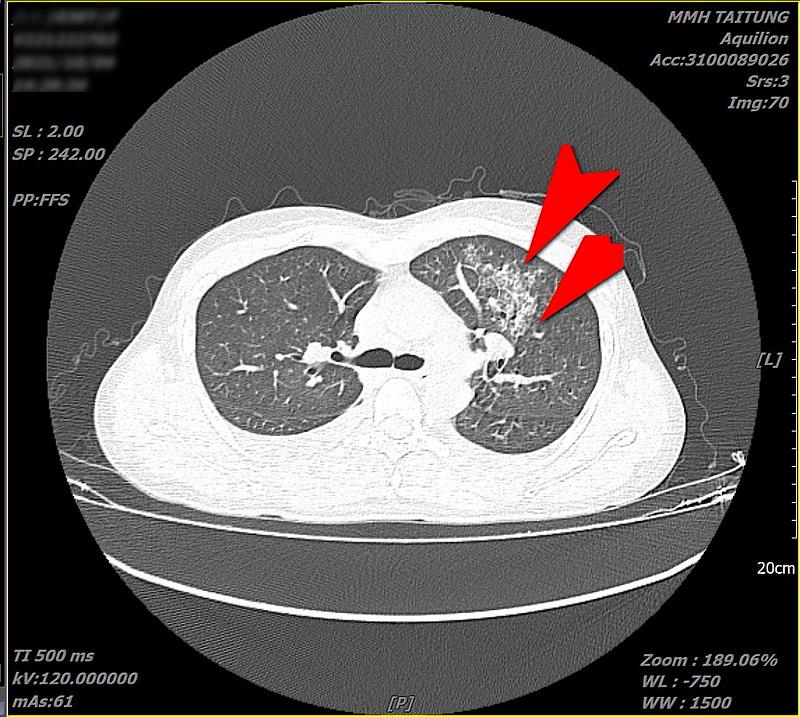

每年三、四月起,恙蟲病例數開始增加,鄭順賢醫師指出,日前收治一位女性病患,因高燒不退、呼吸急喘,先在北部就醫住院治療後要求出院,再到花蓮慈院急診。經過詳細檢查後發現她的右邊腰部有「焦痂傷口」,且肝功能指數異常,雙側鼠蹊部亦見淋巴結腫大,胸部電腦斷層檢查更發現左邊肺部有非典型發炎現象。